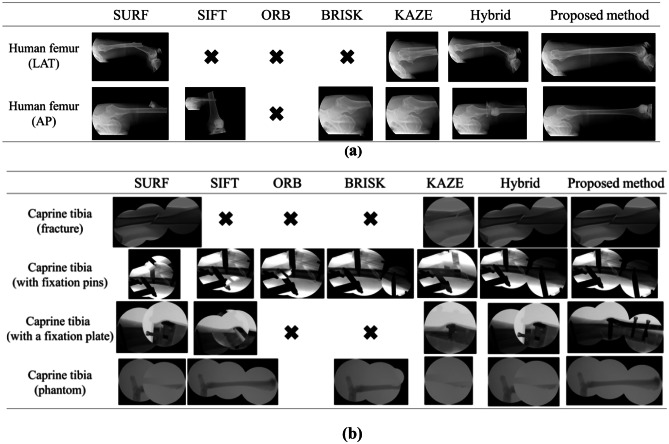

To verify the performance of the proposed method, X-ray image stitching experiments were conducted. Both the conventional and the proposed method were implemented in MATLAB (R2019a, Mathworks) using its toolbox. In the experiment, two types of test images were used: X-ray images of the caprine tibia and the human femur [40]. In the X-ray image of the human femur, anteroposterior (AP), and lateral (LAT) views of the image were used. In the X-ray images of the caprine tibia, the intact and fractured tibia states were used. As shown in Fig. 3, the fractured tibia was from a cadaver, and the intact tibia was a phantom. In addition, to reflect the conditions in an actual operation, fixation pins and the fixation plate, which are indispensable for fracture surgeries, were included in the X-ray images of the fractured tibia.

Fig. 3.

Test images used in the experiments. (a) X-ray images of a human femur (LAT view). (b) X-ray images of a human femur (AP views). (c) X-ray images of a caprine tibia (fracture). (d) X-ray images of a caprine tibia (with fixation pins). (e) X-ray images of a caprine tibia (with a fixation plate). (f) X-ray images of a caprine tibia (phantom)

The test images were simulated X-ray images from the C-arm. The X-ray images were generated following user interventions based on the manual adjustment of the overlap region. Considering the effect of the overlap region, it must be noted that the overlap between the second and third input images in each test image set was narrower than the overlap between the first and second input images. The results of the X-ray image stitching methods performed on the test images in Fig. 3 are shown in Fig. 4. SURF, SIFT, ORB, BRISK, KAZE, and the hybrid method (which combines SIFT and SURF), were used as the conventional methods of X-ray image stitching, and these were compared with the proposed method.

Fig. 4.

Resulting images of the experiments on the test images. (a) X-ray image of the human femur. (b) X-ray image of the caprine tibia

When the results among the conventional methods were compared, the performance of the hybrid method was the best. Based on the experimental results shown in Fig. 4, features from SURF and SIFT are more applicable for X-ray image stitching than features from ORB, BRISK, and KAZE. Thus, it is reasonable that the hybrid method has a better performance for X-ray image stitching compared to the other conventional methods. However, it does not mean that features from ORB, BRISK, and KAZE are unnecessary. When the hybrid method is compared to the proposed method, the proposed method produced more robust panoramic images, as shown in Fig. 4 since more various features are included by integrated feature detection.

When comparing the results in terms of the image content, the stitching mostly failed in the X-ray images that included only bone (i.e., without any accessories). Since sufficient features such as blobs and edges could not be obtained, matched features could not be acquired, and the homography was not estimated. Instances of this result are marked with the symbol “X” in Fig. 4. By contrast, when the X-ray image contained additional accessories, such as fixation pins and a plate, many features could be obtained. However, since features outside the overlap region are matched when the overlap region is narrow, an incorrect homography was estimated. As a result, stitching was conducted but the resulting image was incorrect.

To examine the overlap region, which affects the stitching, the first stitching with the first and the second input images and the second stitching with the second and the third input images were compared. As previously mentioned, the overlap region between the first and the second input image was larger than the overlap region between the second and the third input images. Accordingly, sufficient matched features for the homography estimation were acquired in the first stitching, and a correct homography was estimated as shown in Fig. 4. Specifically, the first stitching outcomes of all of the tested methods of the caprine tibia X-ray images with fixation pins were successful. However, when the overlap region was narrow, as observed in the second stitching outcomes, features were rarely detected within the overlap region. Therefore, the homography could not be estimated.